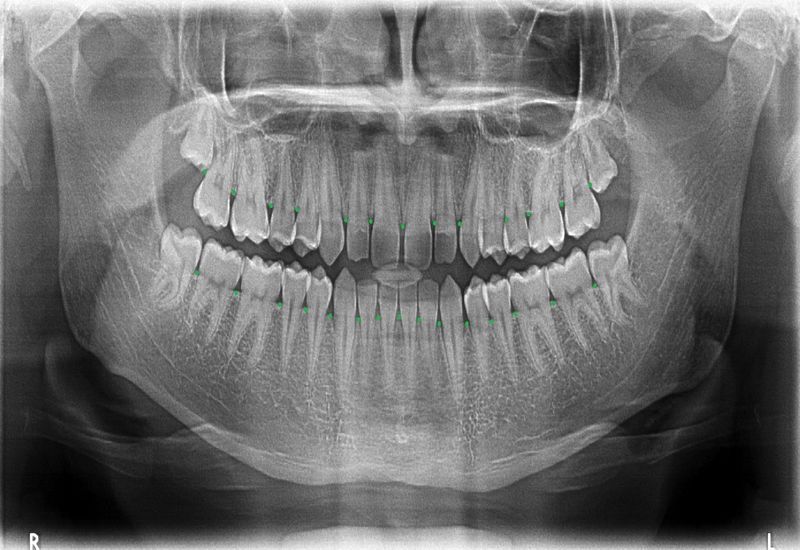

W pierwszej kolejności przeprowadzany jest wywiad oraz badanie, które pozwala na określenie stanu przyzębia i potrzeb leczniczych pacjenta. Lekarz wykonuje badanie przy użyciu specjalnej sondy, które pozwala określić stan przyzębia. Ocenia higienę jamy ustnej pacjenta, a także wykonuje odpowiednie zdjęcia radiologiczne, które umożliwiają pełne zobrazowanie problemu.

Zobacz przypadek naszej pacjentki

Choroba przyzębia, w wyniku zaniku kości doprowadza często do problemów estetycznych. Poniżej prezentujemy przykład kompleksowego leczenia naszej pacjentki, która zgosiła się z zaawansowaną chorobą przyzębia. Zastosowano zabiegi periodontologiczne mające na celu zatrzymanie progresji zaniku kości, a następnie wykonano odbudowy protetyczne w celu poprawy estetyki uśmiechu i uzupełnienia brakujących zębów.